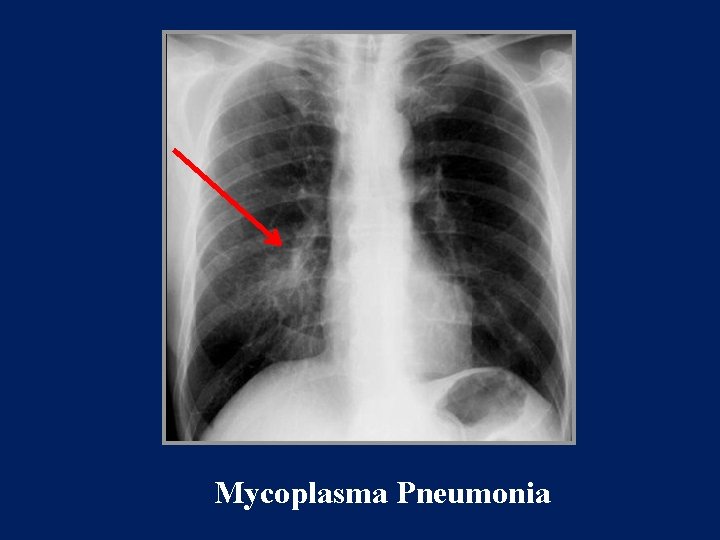

Radiology

Patchy reticular or reticulonodular opacities. Subsegmental and sometimes segmental atelectasis. Hilar adenopathy Pleural effusion

Mycoplasma Pneumonia